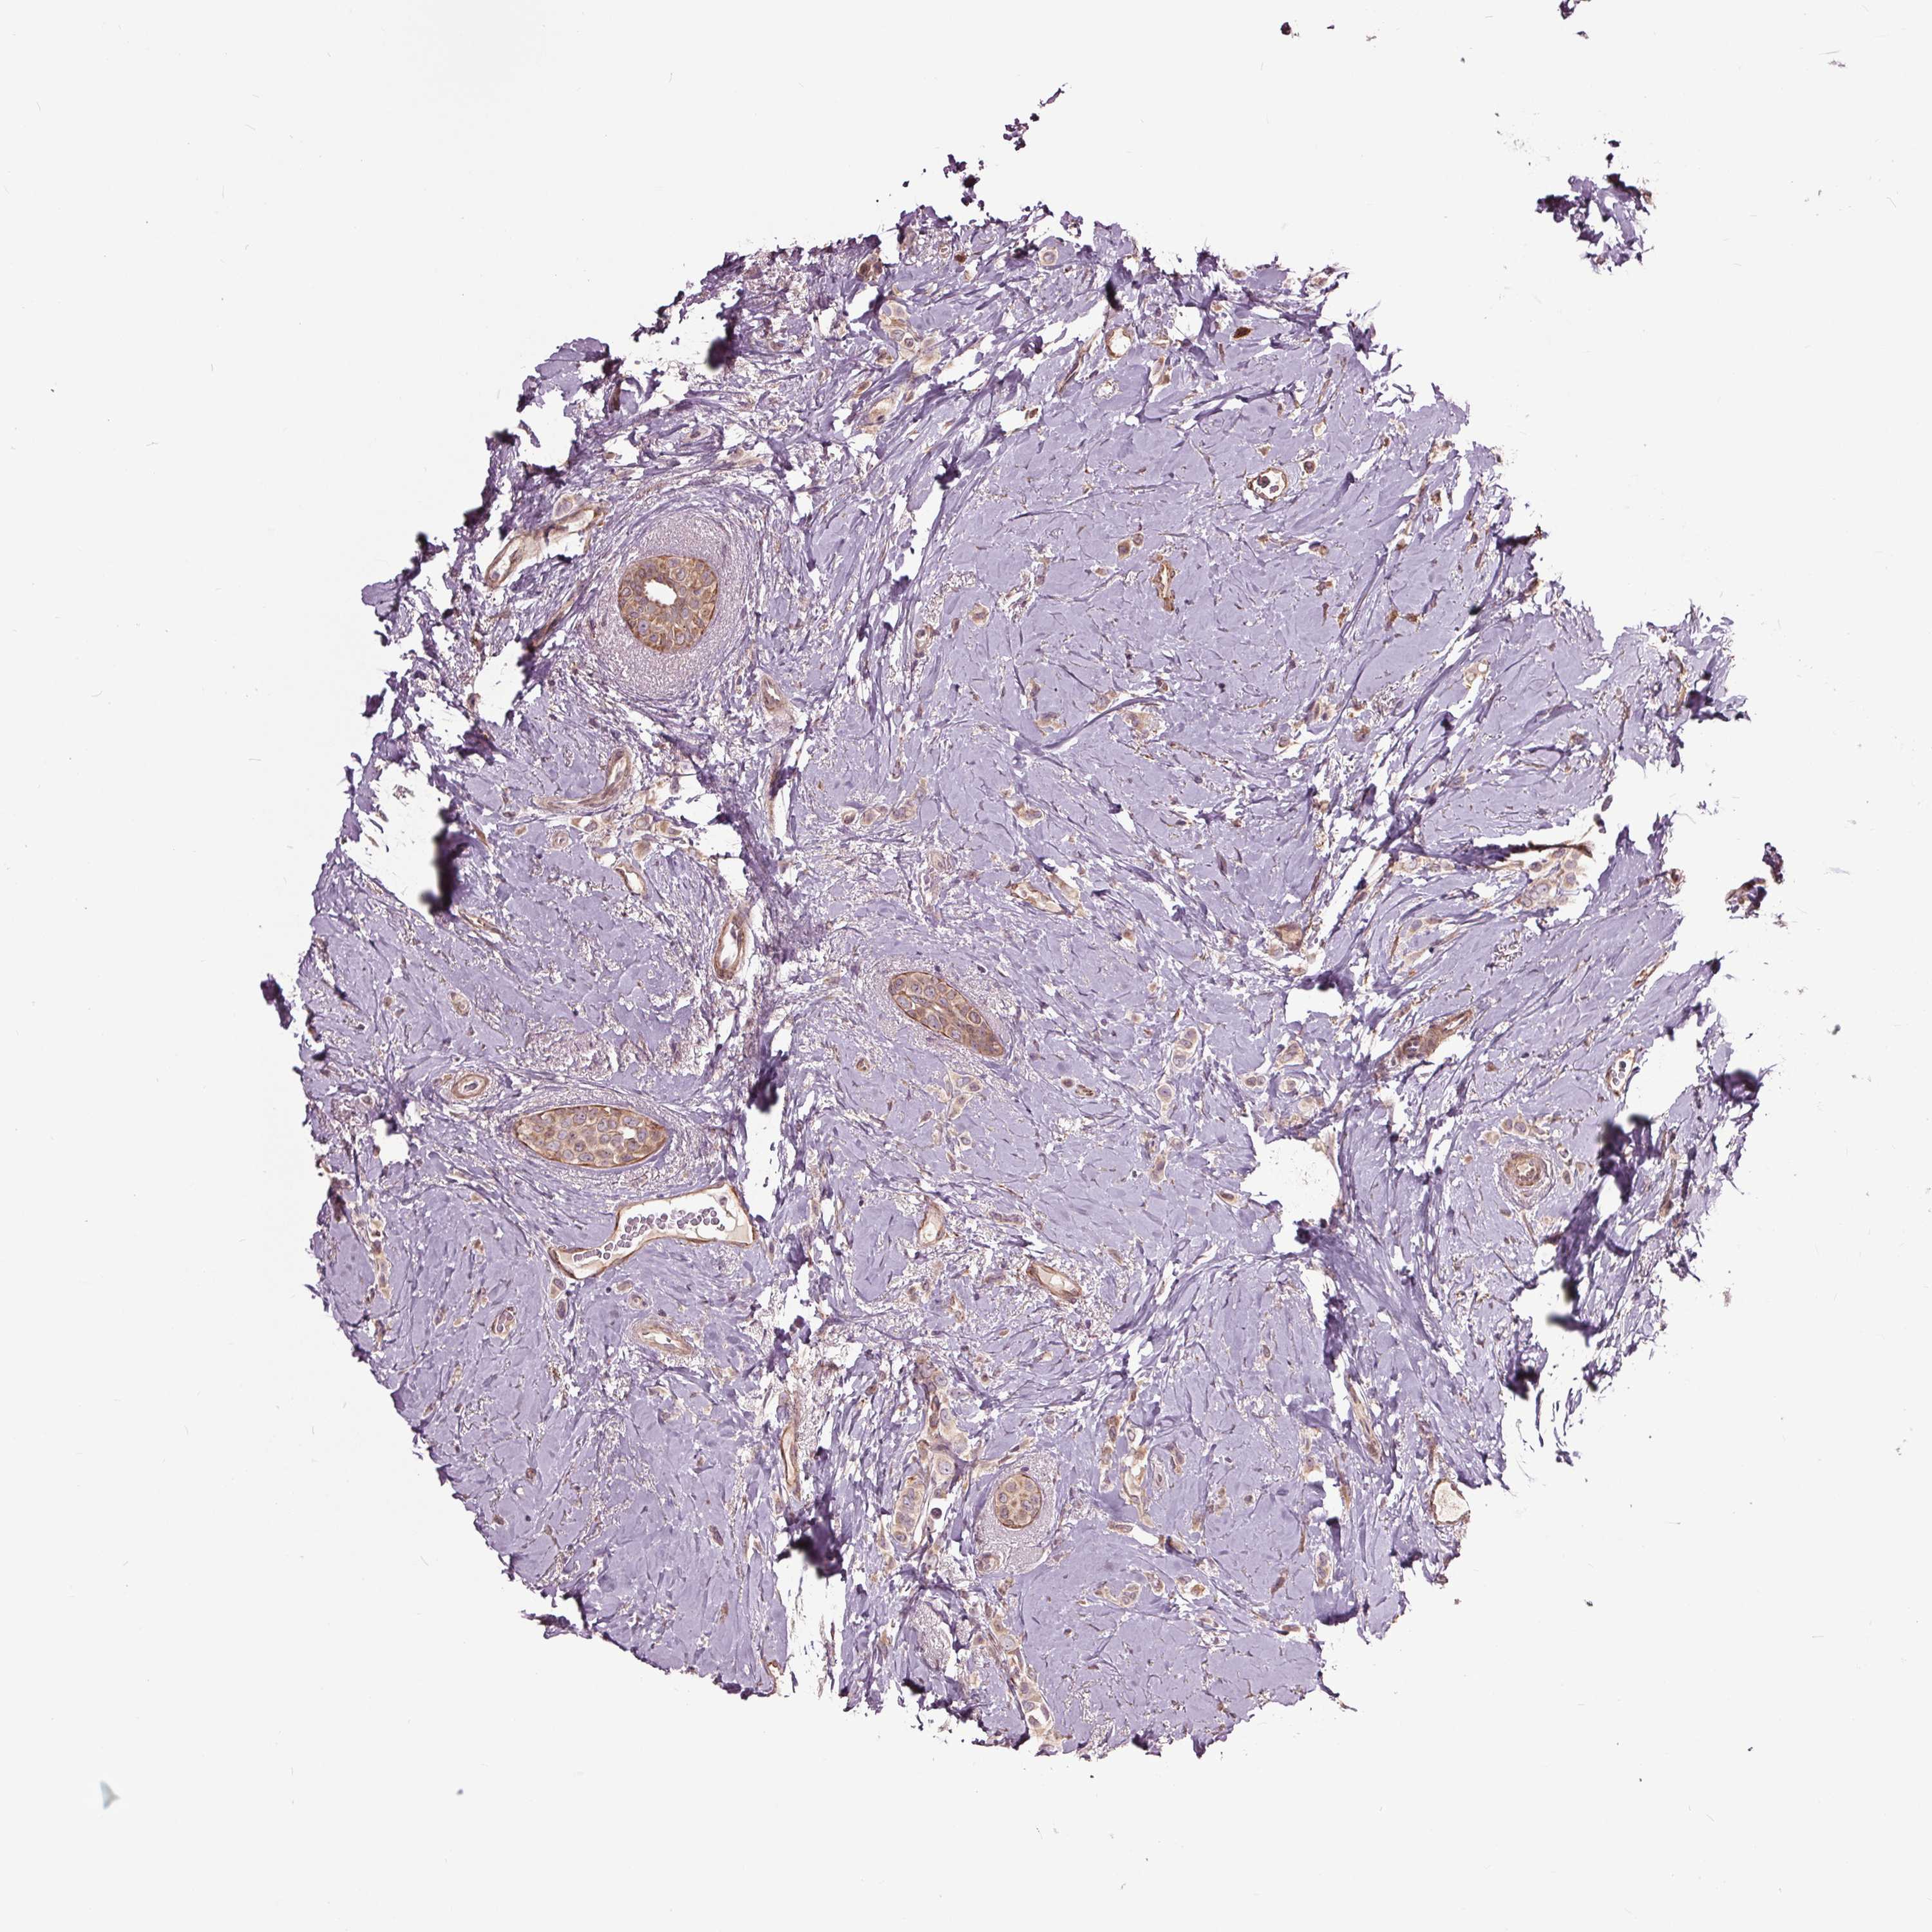

CANCER BREAST CANCER Show tissue menu

BRCA TCGA BRCA VALIDATION PROTEIN EXPRESSION

ANTIBODIES

AND

VALIDATION